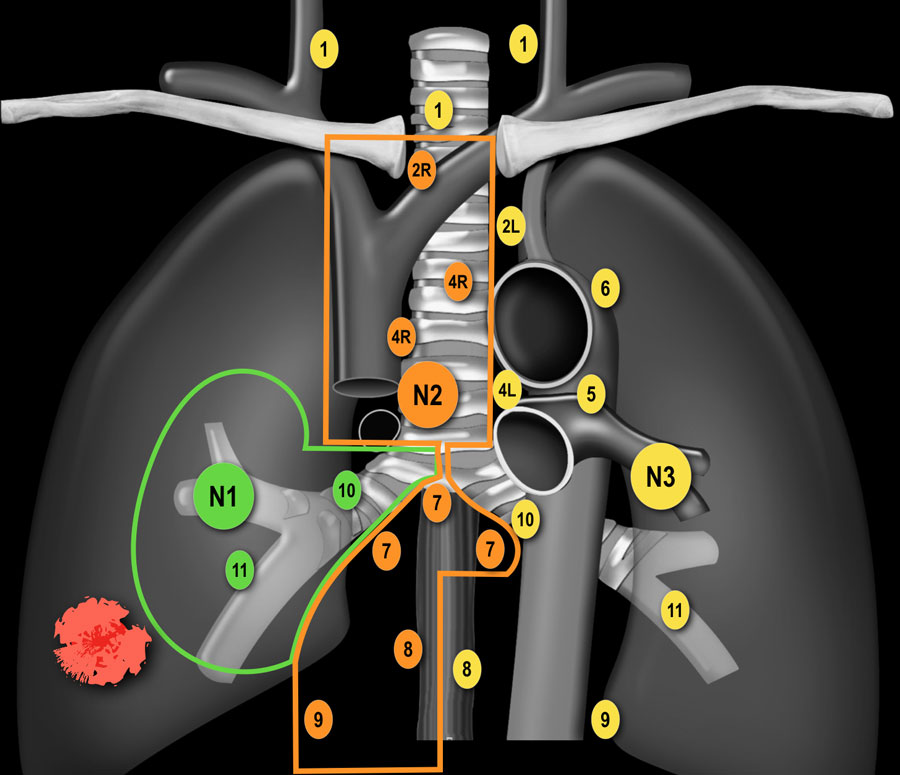

N-стадирование Классификация регионарных лимфатических узлов IASLC 2009 г.

Граница между лимфатическими узлами 10 и 4 группы находится на правой нижней границе непарной вены и на левой верхней границе легочной артерии (отличие N1 и N2 стадий). Достаточно важно разделять лимфатические узлы 1-ой группы и 2/3-ей групп

(отличие N3 и N2 стадий). Граница между группами лимфатических 4R и 4L является левый латеральный контур трахеи, а не срединная линия. Паракардиальные, лимфатические узлы молочных желез, диафрагмальные,

межреберные и подмышечные лимфатические узлы не входят в карту

лимфатических узлов согласно IALSC, несмотря на то, что они редко, но

могут вовлекаться в патологический процесс. ПЭТ/КТ является методом выбора при определении N-статуса. |

N1-стадия

N2 - стадия На данном снимке N2-стадия у пациента с ипсилатеральной медиастинальной

или субкаринной лимфаденопатией. |

N-стадия правое легкое